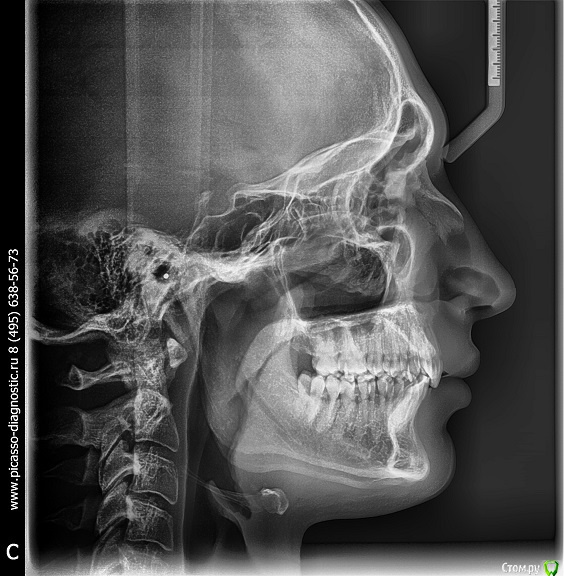

Arseny0111 Опубликовано 27 сентября, 2015 Поделиться Опубликовано 27 сентября, 2015 (изменено) Здравствуйте,в ходе драки получил удар,в верхнюю челюсть,сразу же не значительно сменился прикус и искривилась носовая перегородка.Есть ли на снимках отклонения от нормы?трещина?и т.д.Что с этим делать к кому обращаться?Из исследований дополнительно имеется МСКТ(3D)Спасибо. Изменено 27 сентября, 2015 пользователем Arseny0111 Ссылка на комментарий

Arseny0111 Опубликовано 1 октября, 2015 Автор Поделиться Опубликовано 1 октября, 2015 Здравствуйте,в ходе драки получил удар,в верхнюю челюсть,сразу же не значительно сменился прикус и искривилась носовая перегородка.Есть ли на снимках отклонения от нормы?трещина?и т.д.Что с этим делать к кому обращаться?Из исследований дополнительно имеется МСКТ(3D)Спасибо.Уважаемые доктора,помогите пожалуйста.Неужели нет компетентных специалистов в этой области? Ссылка на комментарий